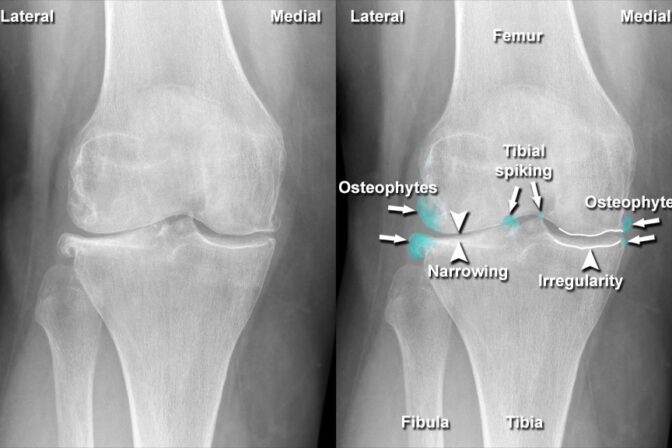

Bone and joint problems can affect people of all ages and significantly reduce quality of life. From knee pain and arthritis to fractures and sports injuries, orthopedic conditions require expert diagnosis and specialized treatment. If you are looking for the Best Orthopaedic Doctors in Vastrapur, Dr. Ruchir Patel at Ortho D Hospital is known for providing advanced orthopedic care with a patient-focused approach.

Knee pain can gradually reduce your mobility and quality of life. Simple activities like walking, climbing stairs, or sitting for long periods may become painful and difficult. For individuals suffering from advanced arthritis or severe knee joint damage, knee replacement surgery offers a life-changing solution. If you are searching for the best knee replacement surgeon in Science City, Dr. Ruchir Patel at Ortho D Hospital is a trusted and highly recommended name.

Expertise in Advanced Knee Replacement in Ahmedabad

Dr. Ruchir Patel is an experienced orthopedic surgeon specializing in total and partial knee replacement surgeries. With a strong focus on precision and patient safety, he has successfully treated numerous patients suffering from osteoarthritis, rheumatoid arthritis, post-traumatic arthritis, and degenerative joint conditions.